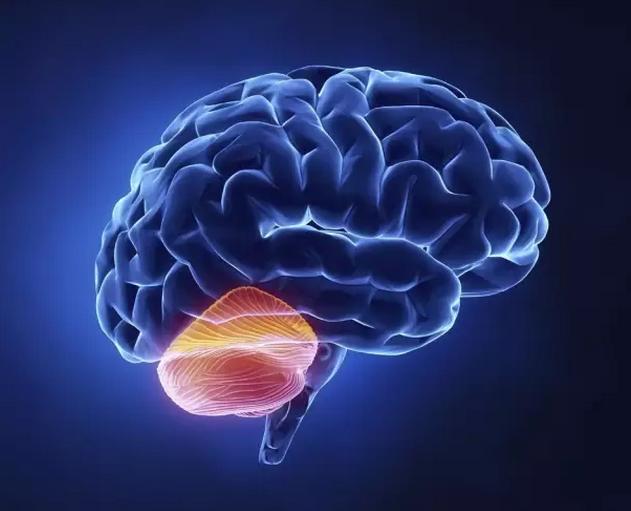

垂体是一个位于头颅内的内分泌器官,是机体神经-内分泌系统所有腺体中最重要和最复杂的器官,是机体内分泌系统的“指挥中枢”(master gland)。大脑底部有一块骨头叫蝶骨,蝶骨上有一个像马鞍形状的小窝,称蝶鞍,脑垂体就舒舒服服地躺在里面。

垂体的上部经垂体柄与下丘脑相连,受下丘脑控制和调节。下丘脑是脑的一部分,位于脑垂体的上方,借助神经脉冲获得有关身体的大量信息;感到有需要时,就分泌称为释放因子和抑制因子的化学物质。这些物质缓慢地传到脑垂体,或刺激脑垂体释放所储藏的激素,或抑制脑垂体释放激素,从而控制身体的生长和发育,调节多项人体功能。